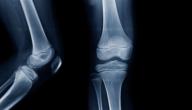

يؤدي الضغط الزائد على العظام إلى كسرها، ومن المناطق المعرّضة للكسر أكثر من غيرها عظام الذراع، ومن أهم المراحل التي تتكون فيها العظام مرحلة الطفولة، فتتم إعادة هيكلة العظام، ومن صفات عظام الأطفال أنها مرنة ولينة، ويوجد في نهايتها جزء من الغضاريف يُعرف بصَفيحَة النُّمُوّ، فتنمو العظام من خلال هذه الصفيحة، ويمكن أن تصاب بالكسور في أي وقت.

على الرغم من أنّ عظام الأطفال معرضة للكسور أكثر من الكبار، إلا أنّ سرعة الالتئام أسرع لديهم؛ بسبب وجود أنسجة ضامة سميكة تساعد على تسريع الشفاء وحماية العظام من الكسر، ومن وظائف هذه الأنسجة إمداد العظام بالدم، لذلك عند تعرضها للكسر تصبح عملية الشفاء أسرع، وتجدر الإشارة إلى تعدّد أنواع الصدمات التي تصيب عظام الأطفال، كالسقوط، أو التعرض لضربة مباشرة، وتختلف قوة تأثير الضربات في العظام فتنتج كسور مختلفة.[١]

• كـَسْر فَوقَ اللُّقْمَة (Supracondylar fractures) : يحدث بنسة تتجاوز 50% من كسور الأطفال حول منطقة الكوع.